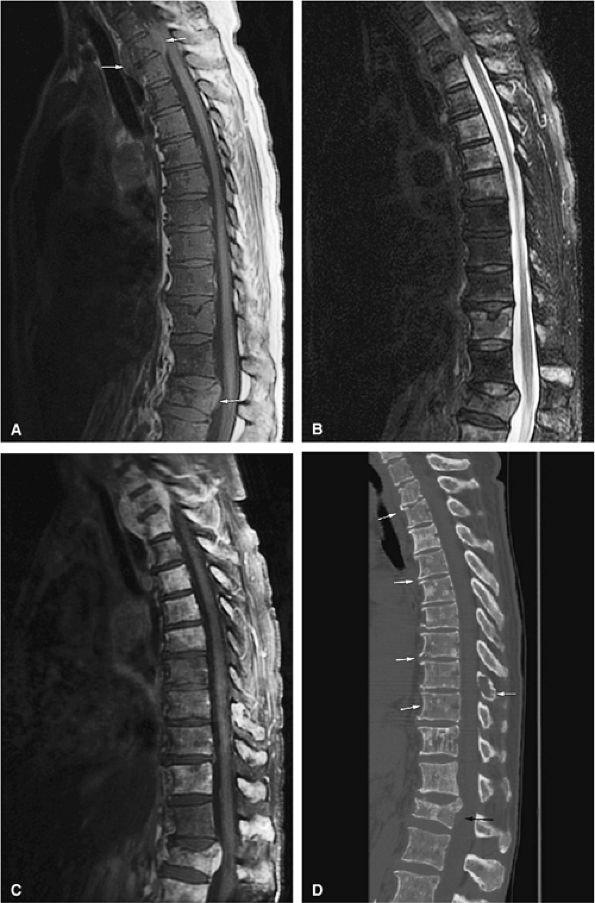

-

![]() |

FIGURE 13.20 ● Extensive myelofibrosis following chemotherapy for leukemia. (A) The bone marrow exhibits diffuse marrow fibrosis, which is of low signal intensity on a sagittal T1-weighted image of the lumbar spine. Low-signal-intensity myelofibrotic marrow is seen on these coronal T1-weighted (B) and fat-suppressed T2-weighted (C) images of the knee. (D) Abnormal sclerosis of the spine, sternum, and ribs is seen on the axial CT image (arrows).